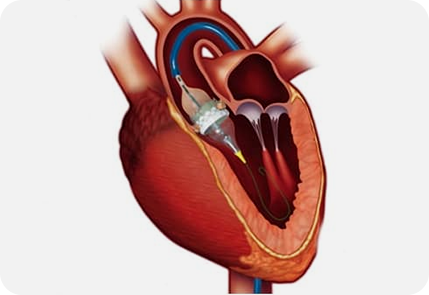

下图为手术治疗瓣膜:

经导管主动脉瓣置换术(Transcatheter Aortic Valve Replacement, TAVR)

CT已成为术前瓣膜置换术(transcatheter aortic valve replacement ,TAVR)规划的首选成像方式。

CT既可以提供主动脉根部(包括冠状动脉)的详细分析,也可以为经导管入路提供潜在的通路 (Ref 41)。

主动脉根部的详细分析

用于TAVR规划的CT数据集必须结合尽量避免瓣膜运动的主动脉环的可视化,

研究证明对于TAVR术前的主动脉瓣的测量最好是CCTA的收缩期,

对于TAVR术前的CTA扫描,扫描范围需要从锁骨下动脉开始延伸到股动脉。